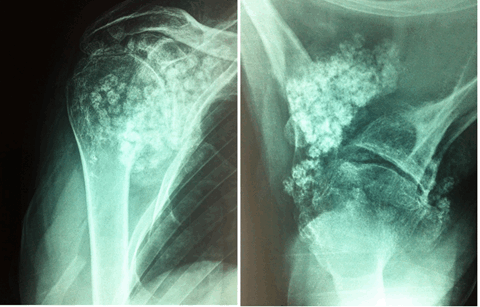

Мужчина 55 лет обратился с жалобами на боль, ограничение активных движений в правом плечевом суставе. Впервые травма в 1983 году, при заведении штанги за голову произошел вывих головки правой плечевой кости. В дальнейшем у больного было около 50 вывихов, которые пациент вправлял самостоятельно. Неоднократно обращался за помощью по месту жительства и в Киевский НИИТО в 2009-2010 гг., установлен диагноз: деформирующий артроз, хондроматоз правого плечевого сустава. Оперативное лечение не проводилось. В марте 2016 года проходил лечение в РНИИТО. При объективном осмотре определялась умеренная гипотрофия дельтовидной мышцы, а также мышц-ротаторов справа. Пальпация болезненна вокруг правого плечевого сустава. Движения резко ограниченны, с хрустом: отведение 25°, сгибание 30°, разгибание 20°, полное отсутствие ротационных движений. По данным рентгенографии правого плечевого сустава от 03.03.16 г.: деформирующий артроз III ст. с массой свободных тел в полости сустава (рис. 1).

Рис. 1. Рентгенограммы пациента при поступлении: снимок правого плечевого сустава в прямой проекции и аксиальной проекции (второй случай)